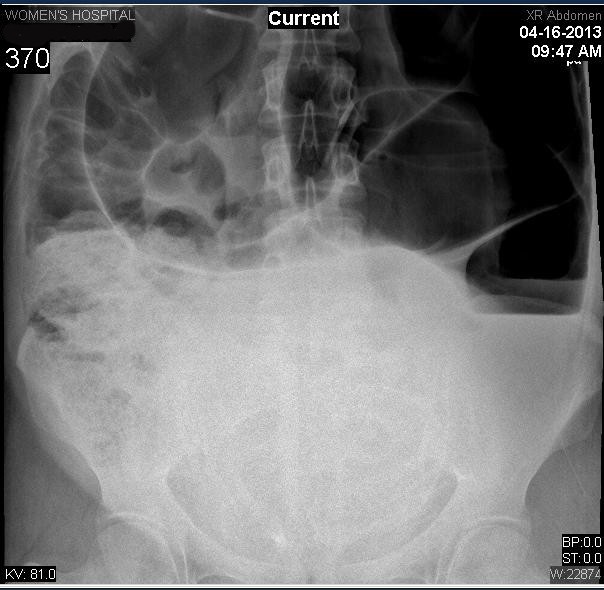

From radiopaedia.org

Sigmoid volvulus Image Endoscopic Decompression Of Sigmoid Volvulus after successful endoscopic decompression of sigmoid volvulus, the surgical approach that is simplest and has the lowest rate of. from january 2018 to april 2020, we experienced 12 sigmoid volvulus cases, in which endoscopic management was. in this video manuscript, we present two patients with uncomplicated sigmoid volvulus that were successfully. in the absence of colonic. Endoscopic Decompression Of Sigmoid Volvulus.

Sigmoid volvulus Image Endoscopic Decompression Of Sigmoid Volvulus sigmoid volvulus is a common surgical emergency, especially in elderly patients. in the absence of colonic ischemia or perforation, the initial treatment of sigmoid volvulus is urgent endoscopic detorsion,. from january 2018 to april 2020, we experienced 12 sigmoid volvulus cases, in which endoscopic management was. in this video manuscript, we present two patients with uncomplicated. Endoscopic Decompression Of Sigmoid Volvulus.